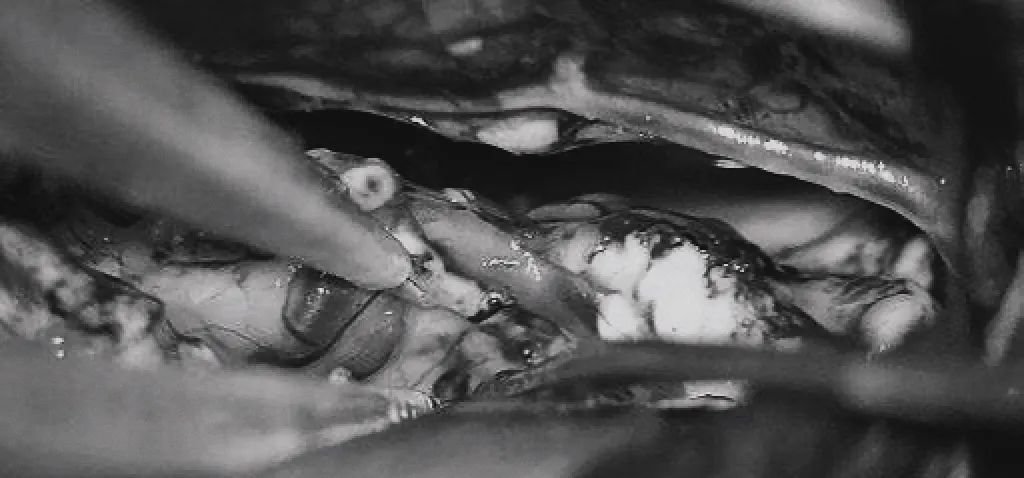

?。╟)雙額開顱,打開縱裂(鼻朝右,中線水平位,重力牽拉右側(cè)半球),顯露胼胝體、CmaA和PcaA。(d)切開胼胝體2.5cm,顯露透明隔內(nèi)的AVM,大致顯露ACA。

(c)雙額開顱,打開縱裂(鼻朝右,中線水平位,重力牽拉右側(cè)半球),顯露胼胝體、CmaA和PcaA。(d)切開胼胝體2.5cm,顯露透明隔內(nèi)的AVM,大致顯露ACA。

▼(e)將AVM后緣向前牽離穹窿。

(e)將AVM后緣向前牽離穹窿。

▼(f)在透明隔底部保留FoM、穹窿和右側(cè)SepV。

(f)在透明隔底部保留FoM、穹窿和右側(cè)SepV。

▼(g)引流靜脈變黑。

(g)引流靜脈變黑。

▼(h)引流靜脈進(jìn)入ICV處電凝。完全切除AVM。

(h)引流靜脈進(jìn)入ICV處電凝。完全切除AVM。